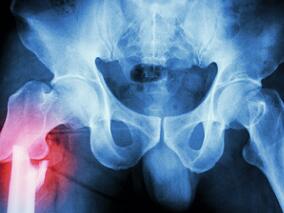

髋部骨折风险随PPI剂量无限升高?

1小时条评论2019年1月,发表于《Osteoporos Int》上的一项观察性研究的Meta分析,考察了质子泵抑制剂(PPI)和骨折风险间的相关性。 综述:研究者对相关性研究进行了一项Meta分析,来量化PPI和髋部骨折风险间相关性的强度。服用PPI的患者比未服用者具有更高的髋部骨折风险(RR...

一文揭晓髋部骨折术后院内感染风险的变化趋势

1小时条评论2019年3月,丹麦和英国学者发表在《J Bone Miner Res》的一项2005~2016年全国研究,调查了髋部骨折术后医院治疗感染风险的增加和基于社区的抗生素使用情况。 研究者旨在检测丹麦2005~2016年髋部骨折术后治疗感染发生率的趋势。 研究者使用丹麦基于人群注册中的个体...